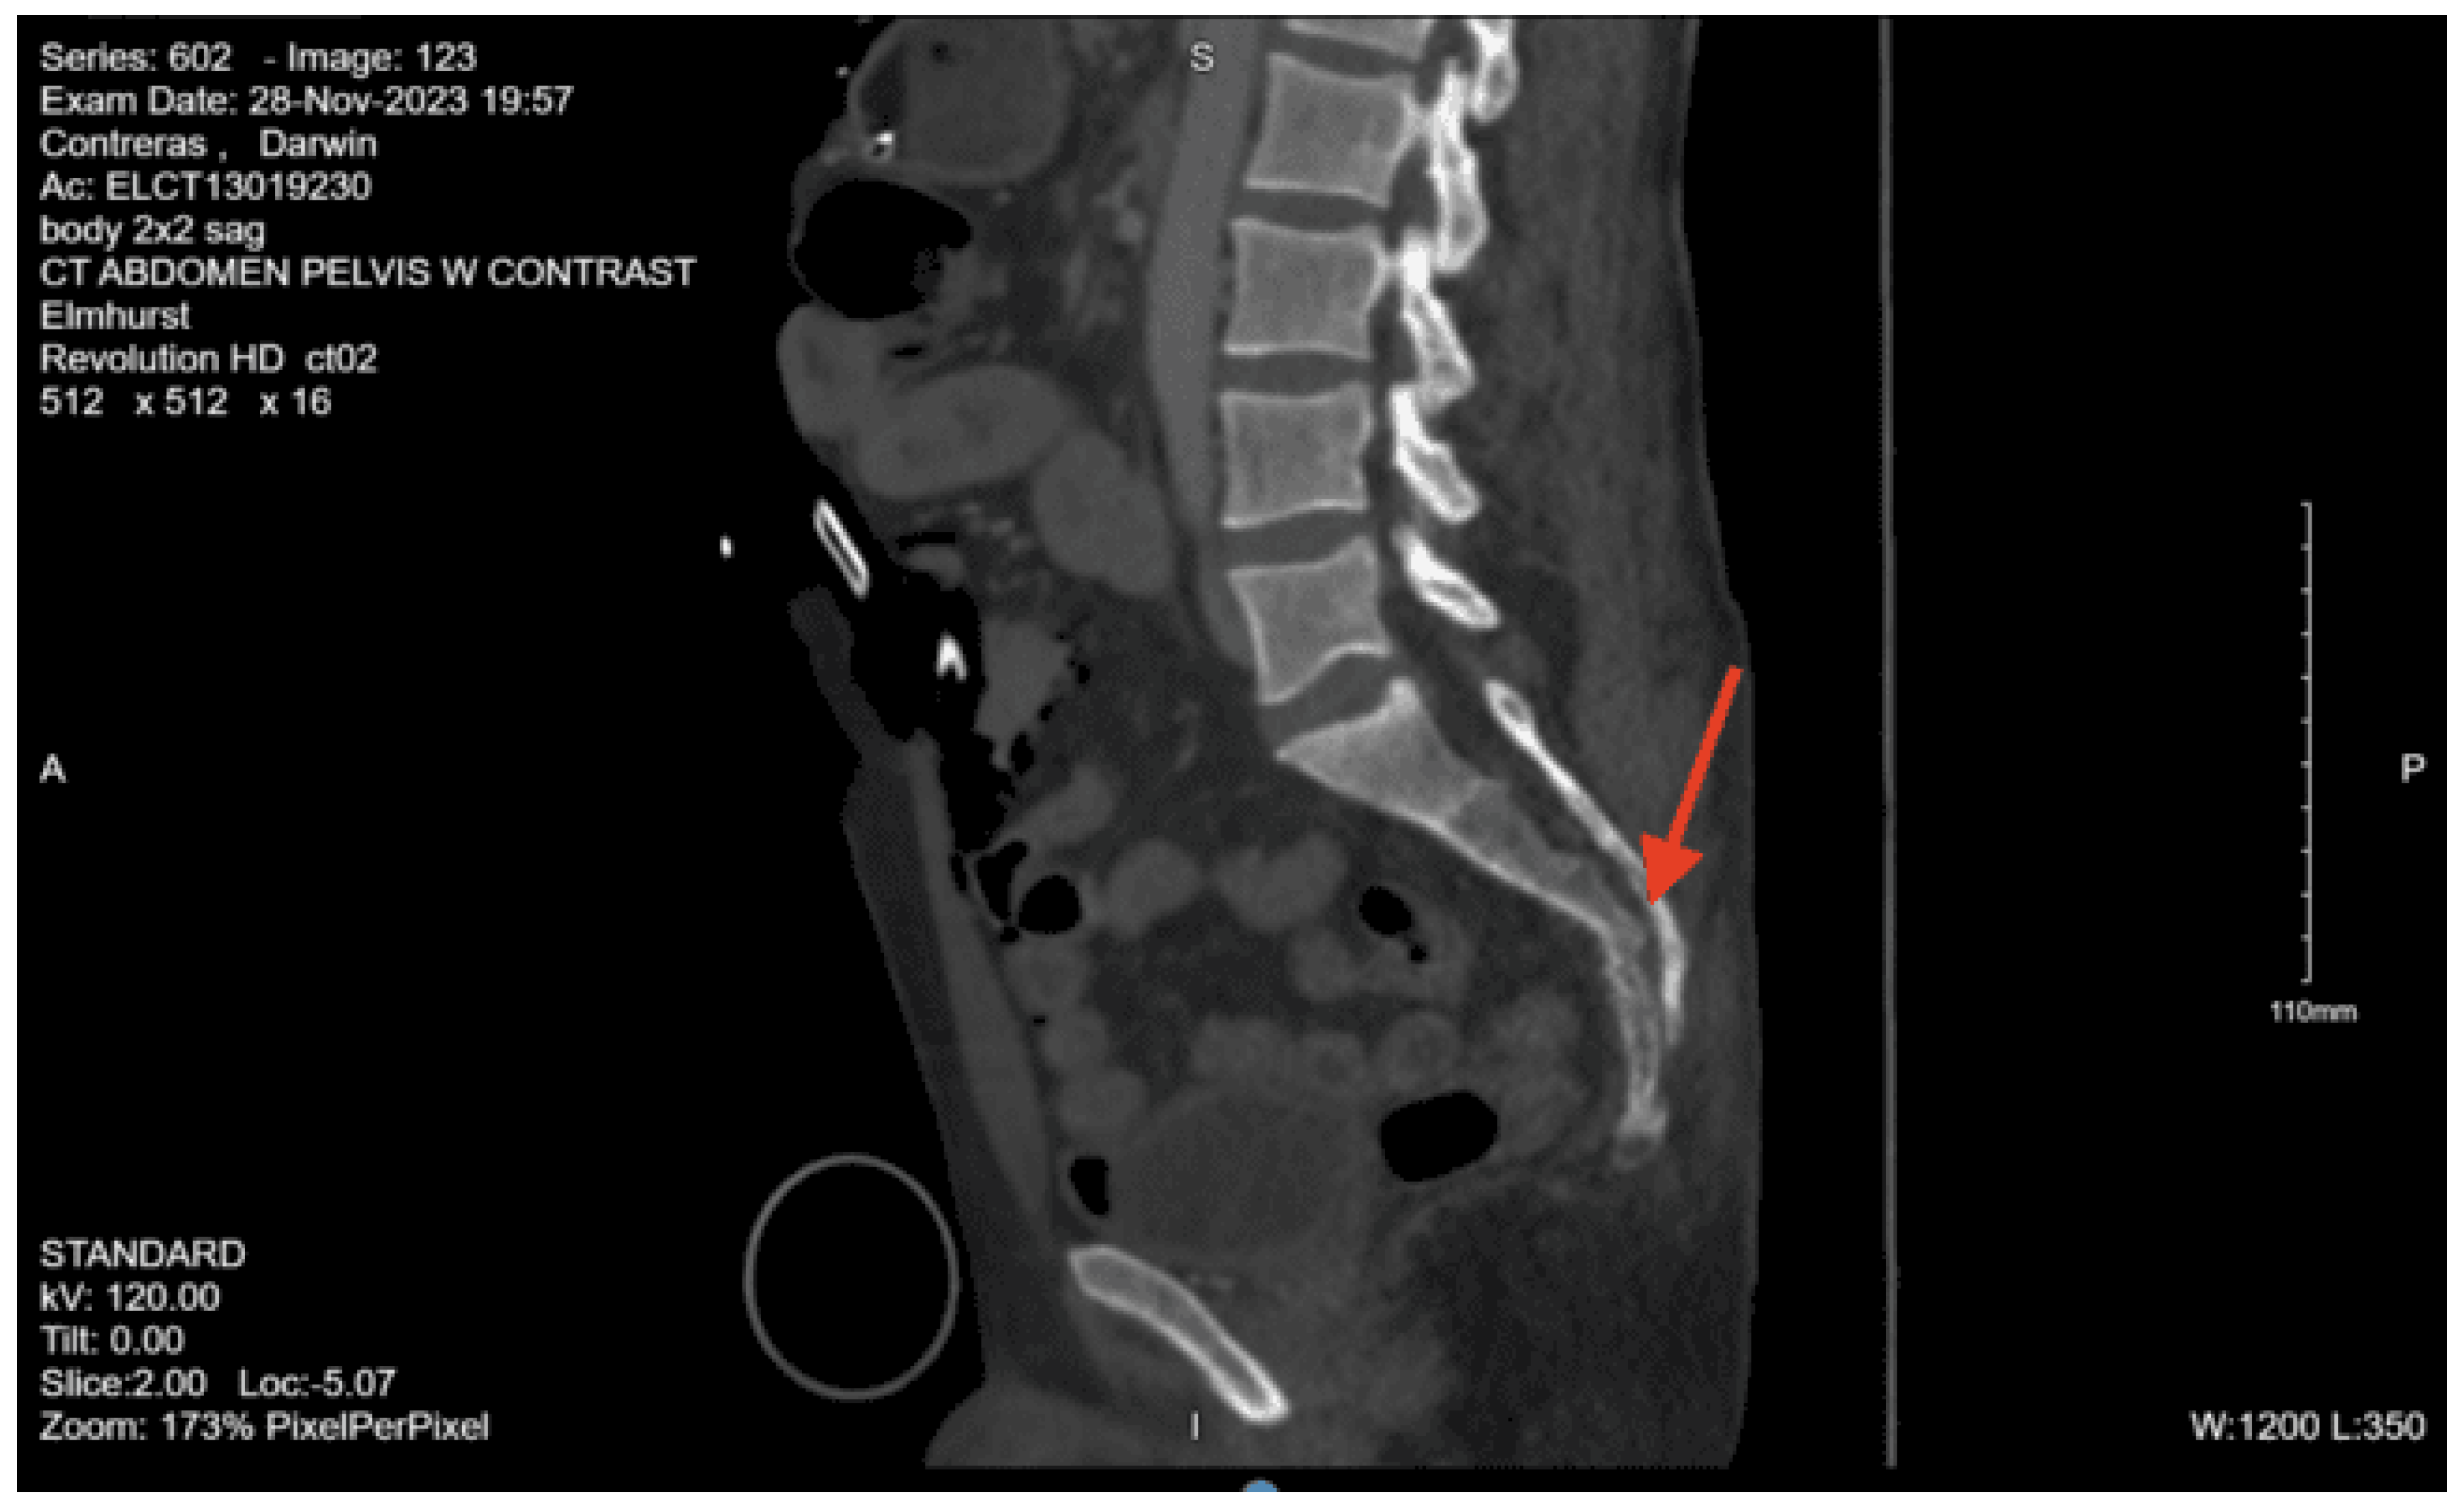

CT abdomen pelvis with contrast: Acute nondisplaced bilateral sacral alar fractures with extension into the sacroiliac joint on the right and probable involvement of the right S3 neural foramen. Amorphous hematoma in the medial left gluteal musculature and subcutaneous fat measuring approximately 3.3 x 6.6 x 7.7 cm. No visceral organ injury.

On initial arrival, his GCS was 14 but declined to 11 (M5 V2 E4) throughout the trauma survey. The patient was then found to have a left blow pupil and was immediately brought in for a CT scan due to concern for intracranial bleeding, and neurosurgery was consulted. While in the CT scanner, the patient had a decline in GCS to 8. The CT head non-con showed a traumatic brain injury, showing significant intracranial bleeding. He was given 5mg of labetalol and, per neurosurgery recommendations, was ordered for Kcentra. A clevidipine drip was started, and he was given hypertonic saline, given the concern for raised intracranial pressure. He was given Keppra and tranexamic acid. The medical team shared the information with the family, and the family, including the next of kin, his wife, chose to pursue medical management and forego surgical intervention and against endotracheal intubation.